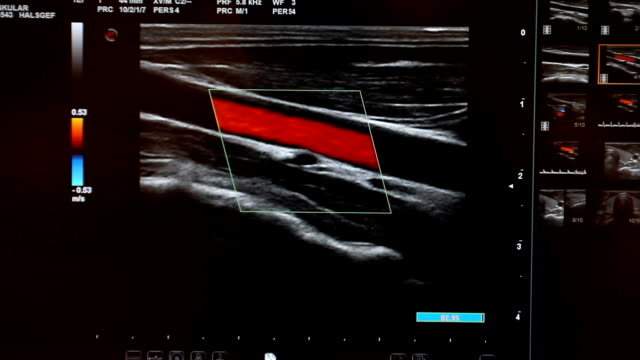

경동맥 초음파 검사는 초음파 기계를 사용하여 경동맥의 상태를 확인하는 검사입니다. 이 검사는 무해하고 비침습적이며, 빠르게 수행할 수 있어 환자에게 불편함을 주지 않습니다. 검사 과정은 다음과 같습니다.

- 초음파 프로브는 고주파 소리파장을 방출하여 경동맥의 이미지를 생성합니다.

- 이미지를 컴퓨터 모니터에 표시하여 의사가 경동맥의 상태를 시각적으로 확인할 수 있습니다.

- 경동맥의 크기와 형태: 경동맥이 충분히 넓고 매끄럽게 유지되는지 확인합니다.

- 혈류 속도: 혈액이 경동맥을 흐르는 속도를 측정하여 혈액순환에 이상이 없는지 확인합니다.

- 혈액 응고물질의 존재: 콜레스테롤과 혈액 응고물질이 경동맥 벽에 쌓여 있는지 확인합니다.